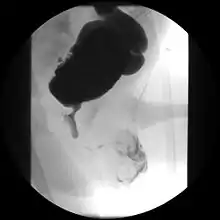

Ultrasound imaging can give information on the shape of the bladder, post-void residual volume, and evidence of kidney damage such as kidney size, thickness or ureteral dilation.[9] Trabeculated bladder on ultrasound indicates high risk of developing urinary tract abnormalities such as hydronephrosis and stones.[10] A voiding cystourethrography study uses contrast dye to obtain images of the bladder both when it is full and after urination which can show changes in bladder shape consistent with neurogenic bladder.[9]